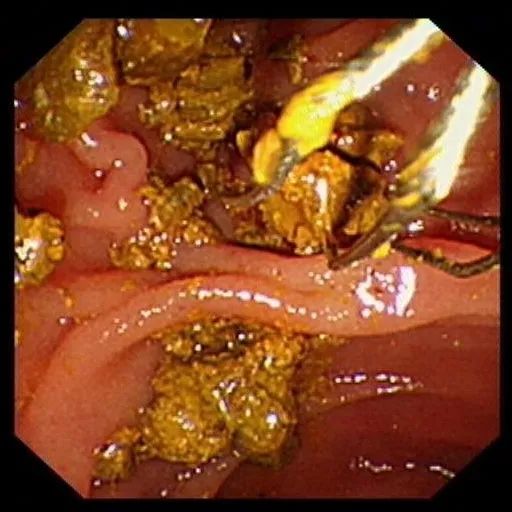

内镜下碎石网篮碎石

取石网篮取净结石碎片扩展阅读